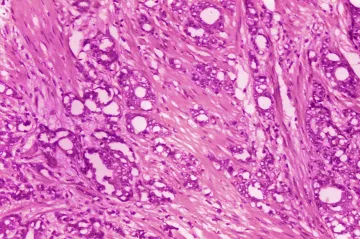

Rakovina prostaty je nebezpečná hlavně při pozdní diagnostice. Od ledna odstartuje screeningový program

Muži ve věku nad 50 let by neměli zapomínat na preventivní vyšetření prostaty. Zdravotníci na čtvrteční konferenci upozornili, že v Česku ročně umírá na rakovinu prostaty 1400 lidí, a to kvůli pozdní diagnostice nádoru. Když se na něj přijde včas, lze dobře léčit. Od příštího roku by měl s prevencí pomoci screeningový program rakoviny prostaty hrazený pojišťovnami.